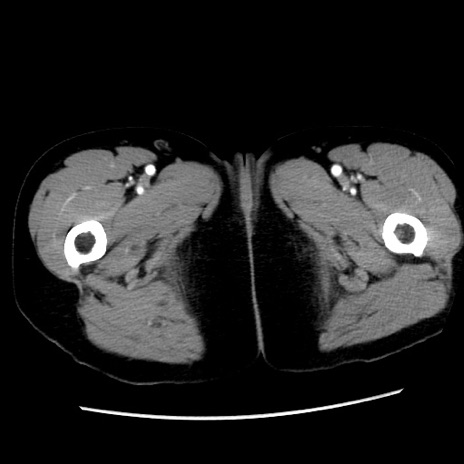

症例10(横断像)

【症例】 50歳代女性

【主訴】 腹痛

【現病歴】前日生レバーを食べた。今朝に排便あり。 昼前に突然発症の腹痛を生じ、当院救急外来を受診した。

【既往歴】 子宮筋腫にてで子宮全摘後

【身体所見】 意識清明、腹部:平坦、軟、下腹部やや左を中心に圧痛・反跳痛あり、筋性防御あり

【データ】WBC 7800、CRP 0.07